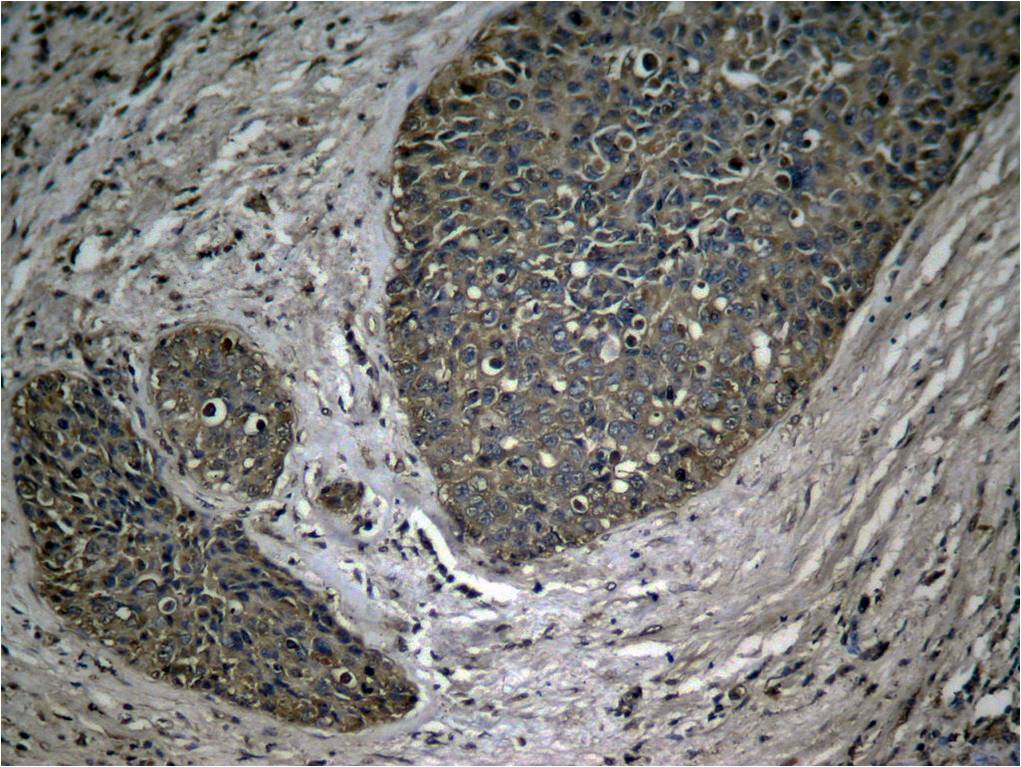

Immunohistochemical analysis of paraffin-embedded human breast carcinoma tissue using NFκB-p65 (Phospho-Ser536) Antibody P40014 (left) or the same antibody preincubated with blocking peptide (right).

Immunohistochemical analysis of paraffin-embedded human breast carcinoma tissue using NFκB-p65 (Phospho-Ser536) Antibody P40014.